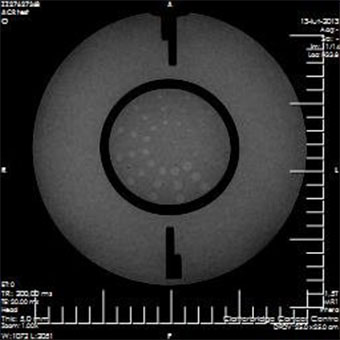

Phantom for comprehensive evaluation of critical imaging parameters of magnetic resonance imaging (MRI) in a time efficient manner. The phantom can be used for the measurement of absolute values for calibration purposes. However, its design is optimized for time efficient daily quality assurance too.

It can be used to measure:- Geometric Distortion

- Spatial Resolution

- Slice thickness and position

- Interslice Gap

- T1 and T2 values

- Estimate of Image Bandwidth

- Low Contrast Detectability

- Image Uniformity

- Signal-to-Noise Ratio (SNR)

- Physical and Electronic Slice Offset

- Point of reference

- Bandwidth: water-fat shift